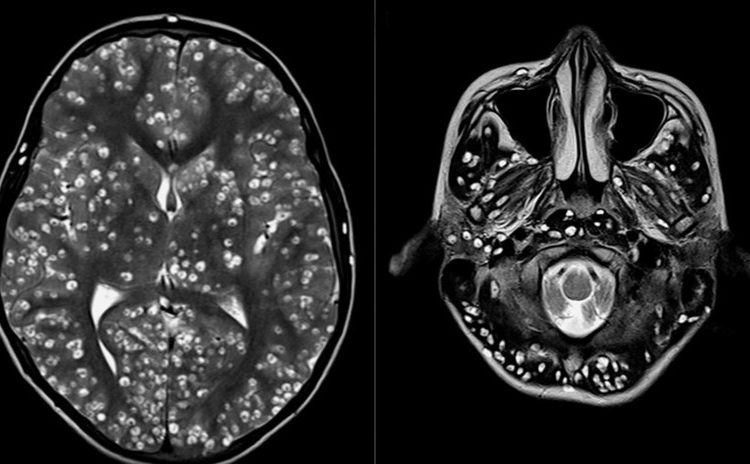

Tras practicarle una resonancia magnética y exámenes de ultrasonido, los especialistas encontraron que la corteza cerebral y el tronco encefálico del paciente estaban llenos de larvas.

El muchacho padecía neurocisticercosis, una enfermedad parasitaria originada cuando una persona ingiere huevos microscópicos de una tenia porcina y que afecta al tejido muscular. De ahí los parásitos se propagan al cerebro. Los personas infectadas pueden pasar mucho tiempo sin presentar síntomas.